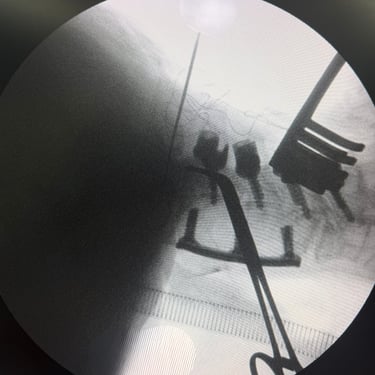

🧠 Cirugía de Revisión Cervical: Estabilidad Posterior en Seudoartrosis y Enfermedad del Segmento Adyacente.

La seudoartrosis cervical con subsidencia del cage y enfermedad del segmento adyacente genera dolor e inestabilidad. La artrodesis cervical posterior con tornillos a masas laterales y pediculares es una técnica eficaz para lograr una fijación sólida, mejorar la estabilidad y aliviar los síntomas neurológicos.